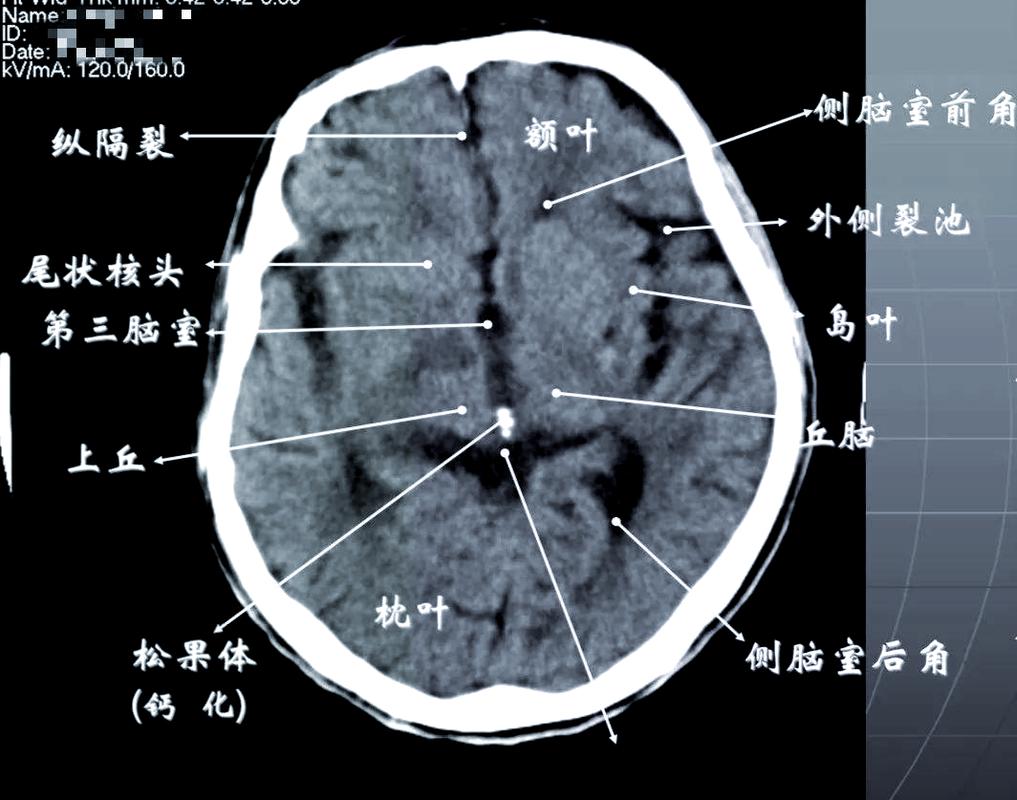

基础篇:脑CT报告单上,这些“名词”你必须知道

在看图之前,我们首先要了解CT报告单上常见的“黑话”,一张标准的脑CT报告单通常包含以下几部分:

- 脑沟、脑裂、脑池: 大脑表面的沟壑和腔隙,里面充满脑脊液(密度低,呈黑色),正常情况下,这些结构清晰。

- 脑室: 内含脑脊液的腔隙,如侧脑室、第三脑室、第四脑室,正常时对称,大小适中。

- 中线结构: 指大脑正中的结构,如透明隔、第三脑室、脑干等,正常时居中。